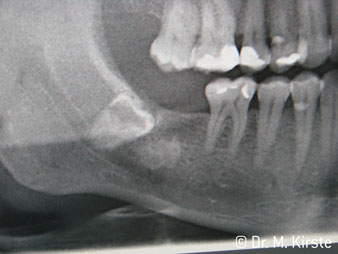

La scelta dell'angolo di 45° del contrangolo offre numerosi vantaggi in sede di utilizzo. I colleghi chirurghi, per i quali è stato messo a punto in primo luogo il contrangolo, noteranno in fretta la possibilità di lavorare in modo molto mirato. In particolare, durante l'estrazione dei denti del giudizio (Fig. 2), non sono necessarie estese resezioni del tessuto molle nell'area della guancia (Fig. 3). La forma della testina del contrangolo, insieme a lievi rotazioni della stessa durante la preparazione, permettono di lavorare in modo rapido e sicuro nella regione retromolare.

La concezione professionale del sistema di cuscinetti nel cuore della testina del contrangolo assicura un funzionamento silenzioso delle frese; durante l'estrazione di denti e radici (Fig. 4 - 9) si ottiene un taglio estremamente preciso e stabile.